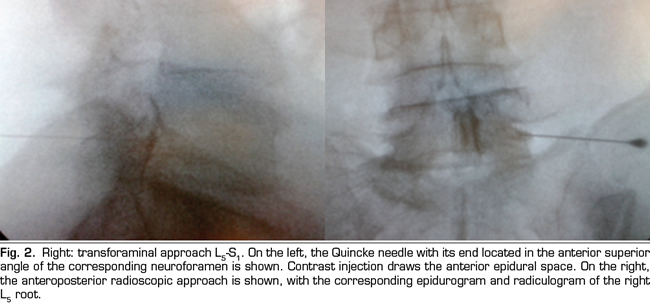

Figure 2